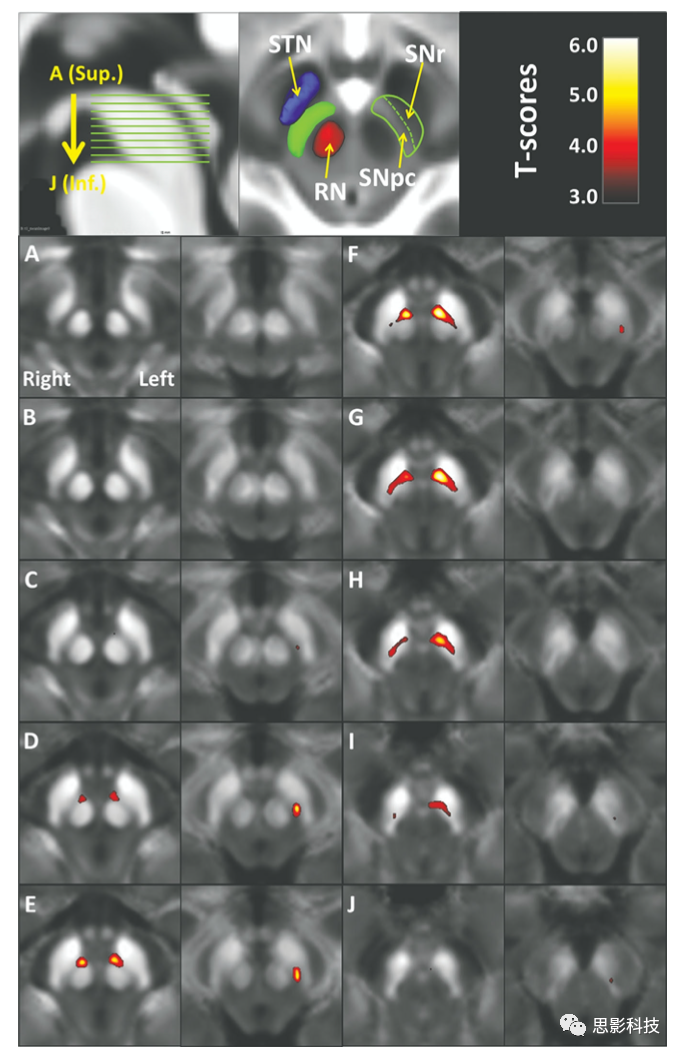

图示:阈值P<0.05(基于体素的Bonferroni校正)的基于体素的t值图显示,QSM(列1和3)和R2*(列2和4)中的铁含量均增加。

背景:帕金森氏病的病理特征是黑质致密部中的多巴胺神经元丢失和铁超载。基于磁共振成像R2*的变化的研究发现,PD患者中脑铁含量增加。由于定量磁化率测绘是一种测量铁含量的新型MRI方法,因此本研究将其与R2*进行了比较,以评估PD中脑的变化。

方法:从47名PD患者和47名健康对照中获得了定量磁敏感成像和R2*图。通过在标准化空间中使用基于体素的方法和感兴趣区域的方法来分析中脑磁敏感性和R2*值,并与包括病程、统一的帕金森疾病分级量表(UPDRS)I、II和III得分以及左旋多巴等效的每日剂量在内的临床数据一起进行分析。所有研究都是在PD患者“服药”期间完成的。

结果:与对照组相比,PD患者的右中脑和左中脑的磁敏感性值均显著增加,位于与红色黑质对应的红色核的腹侧。该区域的磁敏感性值与疾病持续时间,UPDRS II和左旋多巴等效日剂量显著相关。相反,R2*仅在左侧外侧黑质致密部的较小区域显著增加,与临床参数无显著相关性。

结论:定量磁敏感成像的使用显示出与临床PD状态相关的显著性黑质变化比R2*更敏感。这些数据表明,定量磁敏感成像可能是评估PD中脑铁水平的优于R2*的成像生物标记。